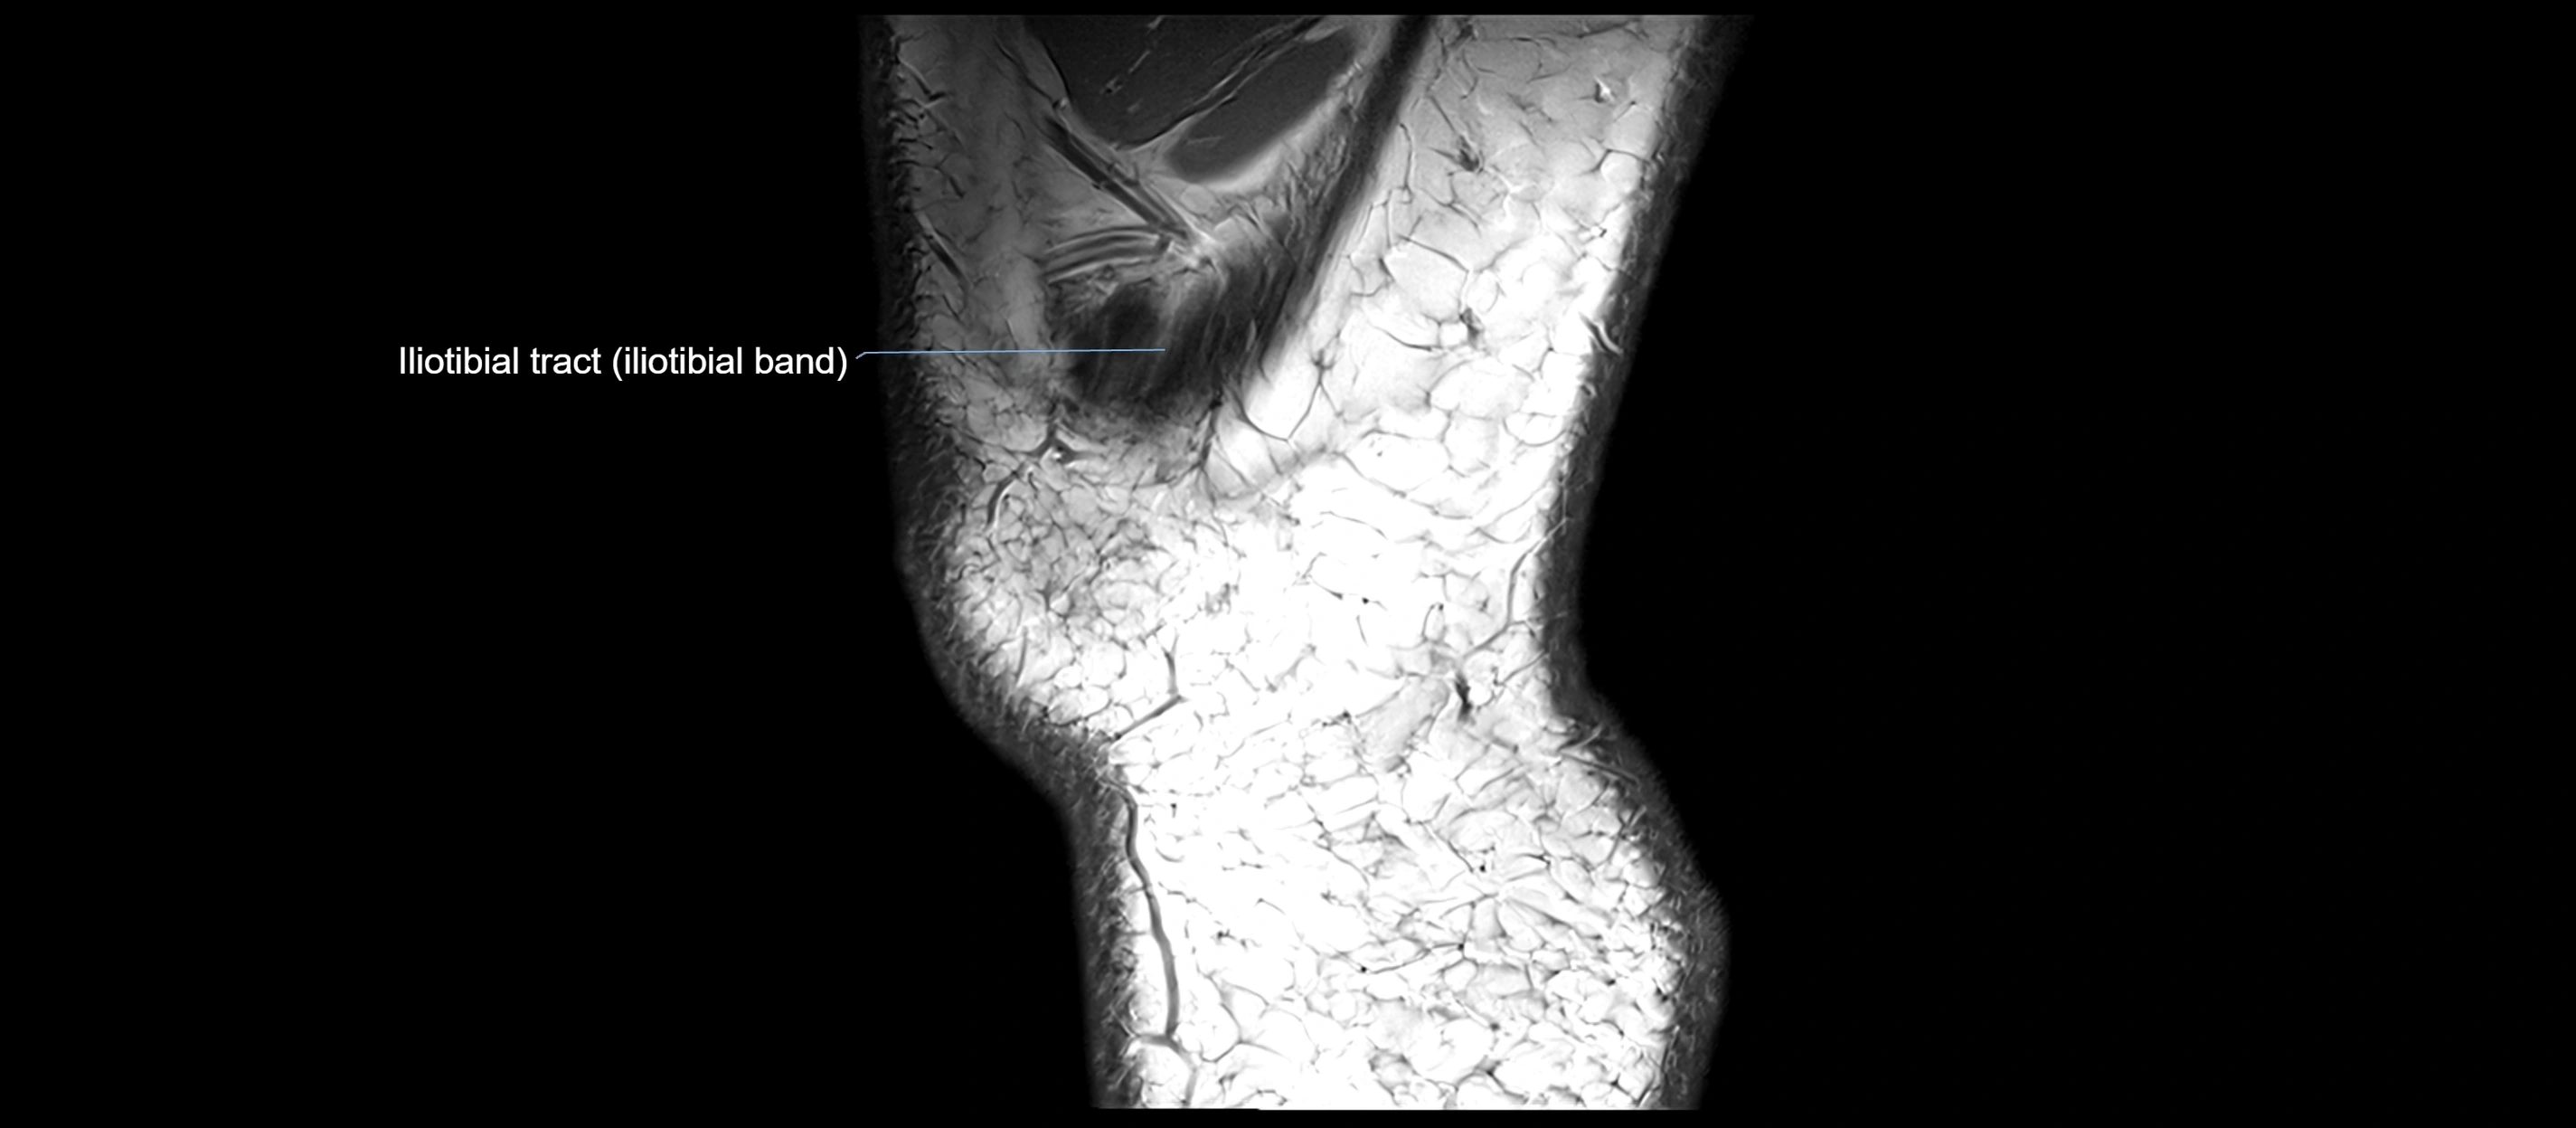

MRI images

image